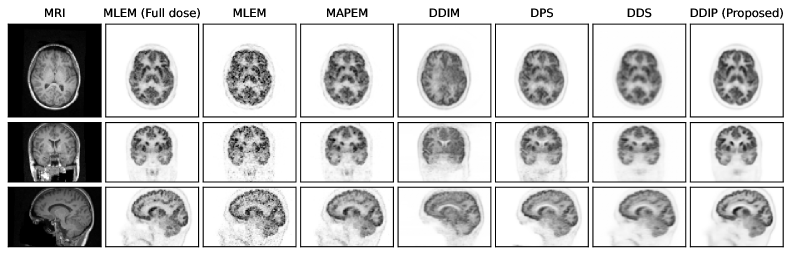

Refer to caption

Figure 10: Reconstruction results of three orthogonal slices of the clinical [F18{}^{\text{18}}\text{F}]FDG data using a diffusion model pretrained on the early-10-mins [F18{}^{\text{18}}\text{F}]MK-6240 tau datasets.

Fig. 6 presents the reconstructed results for different methods. Result of the DDIM method demonstrates that the pretrained score function effectively captured the distribution of the simulated [18F]FDG contrast. Traditional MLEM and MAPEM suffered from high image noise under low-count conditions. In contrast, DPS, DDS and the proposed method produced images with lower image noise; the proposed method more accurately preserved gray matter structures and better recovered gray–white matter contrast compared to DPS and DDS.

Figure 10 shows reconstructed images of the clinical [18F]FDG data using different methods. The DDIM approach produced an early 10-minute [F18{}^{\text{18}}\text{F}]MK-6240 tau PET contrast that closely aligned with the structural features of the MR prior. DPS, DDS and the proposed method yielded images with lower noise levels compared to MLEM and MAPEM. The reasonable performances of DPS and DDS may be due to the relatively close distributional similarity between the early 10-minute [F18{}^{\text{18}}\text{F}]MK-6240 dataset used for training and the [18F]FDG clinical data, as suggested by the visual resemblance between the DDIM outputs and the FDG images.